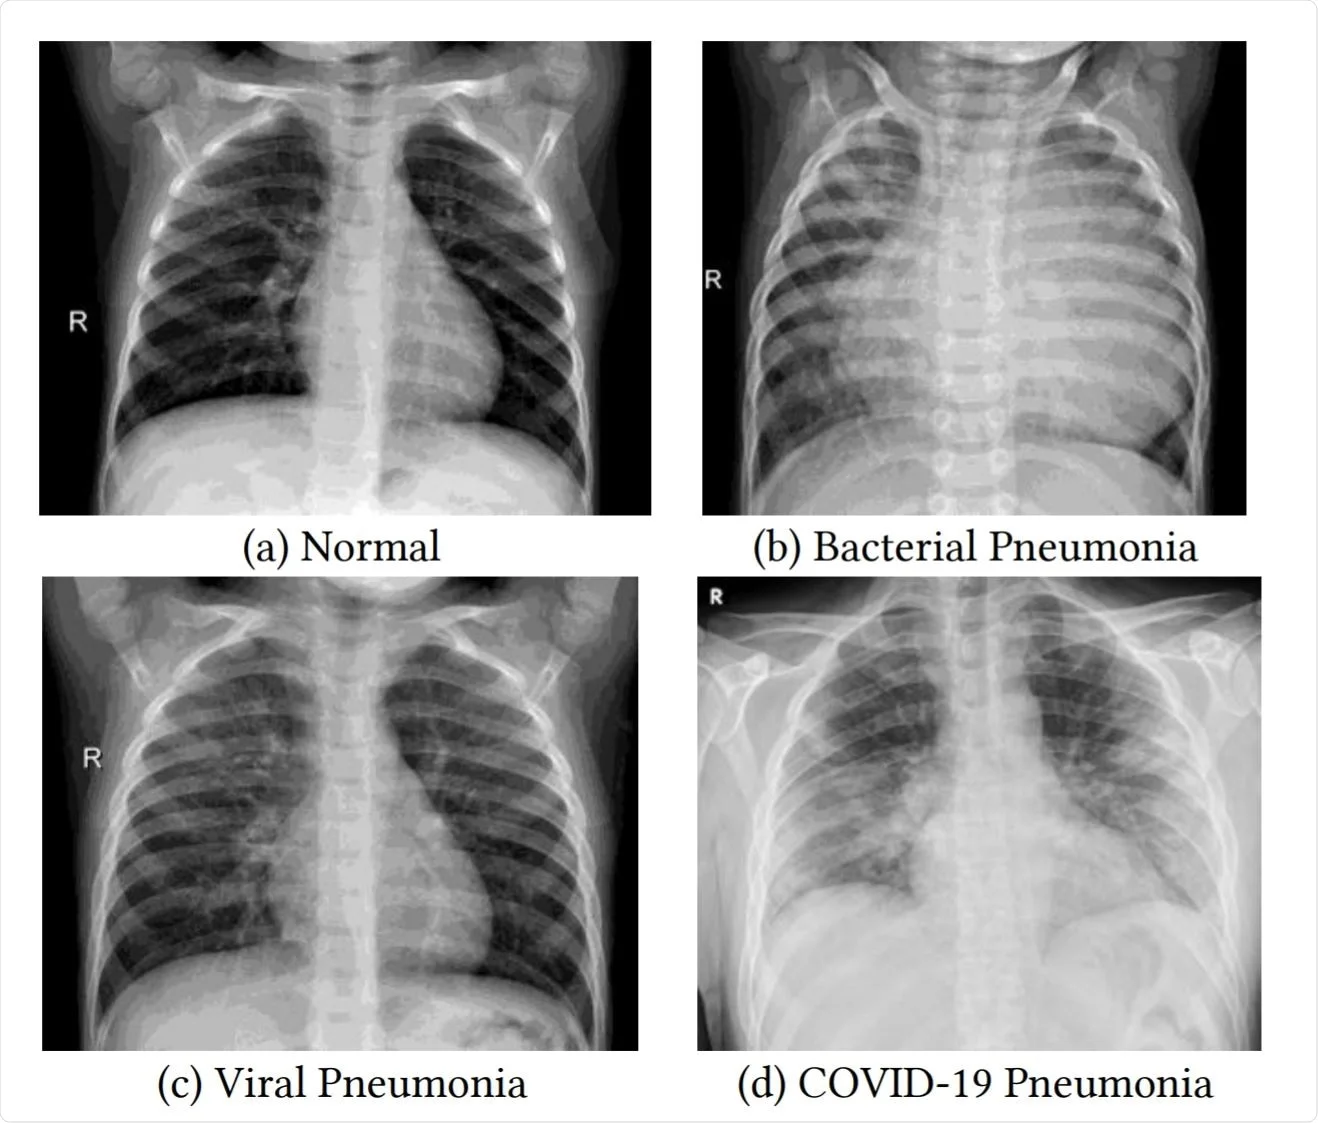

Screenshot of Respiratory Illnesses Classification in Lung X-Rays

Respiratory Illnesses Classification in Lung X-Rays

Developed a convolutional neural network to classify lung X-rays into four categories (COVID-19, viral/bacterial pneumonia and normal). Optimized model performance by comparing VGG-16 vs. VGG-19 architectures over 100 test and train epochs.